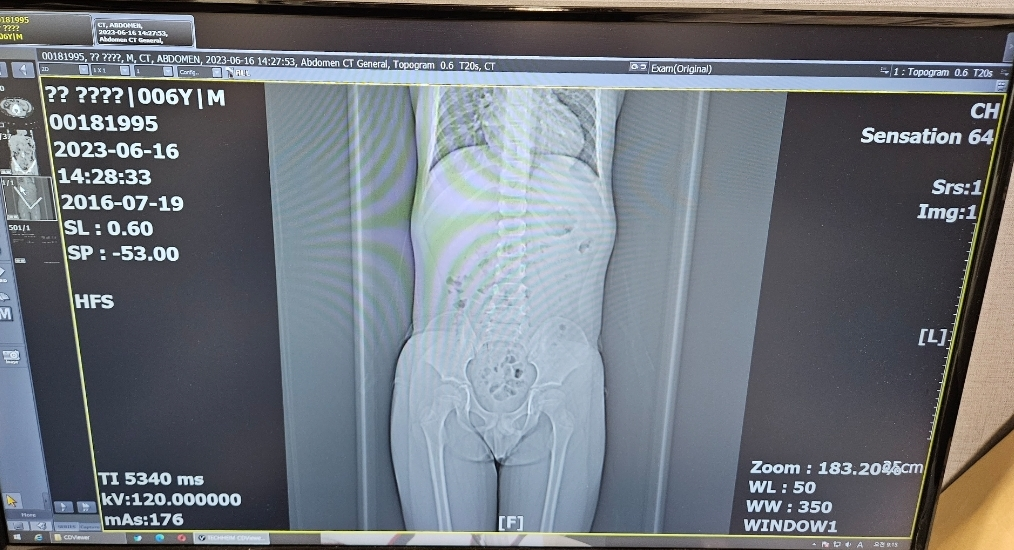

아이의 복부 CT 촬영으로 방사선 노출량이 걱정스러우시군요.

위의 DLP를 mSv로 변환하면 5.5mSv 정도가 나옵니다. 걱정하실 정도는 아니오니 너무 염려하지 않으셨으면 좋겠습니다.